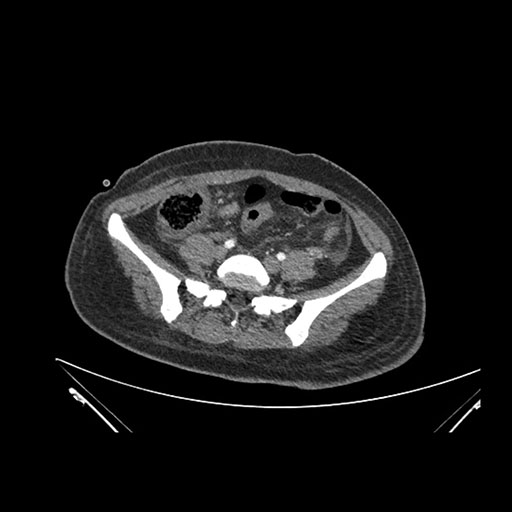

Axial Arterial

Imaging analysis

Based on initial findings, which issue(s) would you be most concerned about?